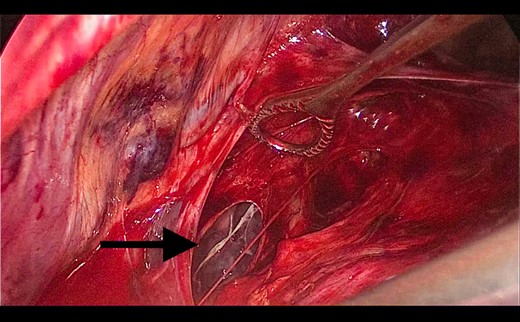

A 73-year-old male patient with a clinical history of COPD, lung emphysema and a 30-year smoking history was admitted to the ED due to a 24-h clinical picture of dyspnea immediately following a sudden bout of dry coughing. Physical examination showed a dyspneic patient, tachypnea of 25 rpm, heart rate of 85 bpm and blood Pressure of 135/75 mmHg along with central cyanosis. Chest exam showed a hyper-resonant right hemithorax along with reduced breath sounds. Initial chest X-ray revealed a large right-sided pneumothorax (Fig. 1). A right chest tube was placed in the ED. Emergency echocardiogram had no significant findings and spirometry showed suspected patterns of obstruction. Following patient stabilization, a high-resolution chest computed tomography (HRCT) was performed revealing extensive pan lobar emphysema throughout both lungs, para septal emphysema in both the anterior upper lobes and herniation of a left lung bullae through the anterior mediastinal pleura along with a right-sided pneumothorax with the chest tube in place with persistent air space (Fig. 2). The patient was taken to surgery where a right video-assisted thoracoscopic (VATS) approach showed severe lung emphysema and a contralateral herniated left lung bulla through the mediastinal pleura anterior to the pericardium (Fig. 3). Right pleurodesis was performed using Talc and a left posterior thoracoscopy showed a severe emphysematous left lung with a lingular herniated bulla to the right hemithorax through an anterior mediastinal pleural defect along with pleural adhesions (Figs 4 and 5). Thoracoscopic hernia reduction was performed along with bullectomy using 60 mm mechanical sutures (Fig. 6). Chest tubes were removed on POD 3 (right) and POD 4 (left). The patient had significant respiratory improvement and was discharged on POD 5.

Thoracoscopic view from left side of transmediasinal hernia of pulmonary bulla after reduction (asterisk).

Thoracoscopic view from left side of thoracoscopic bullectomy.